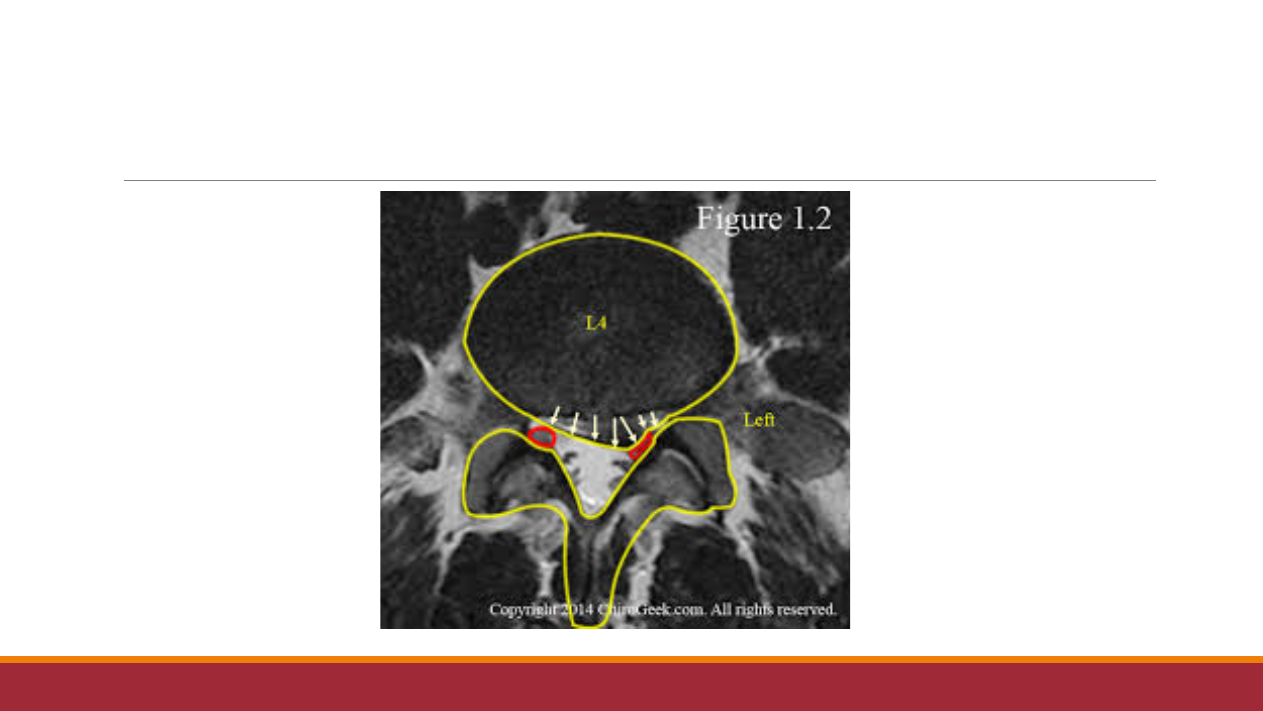

型

腰

椎

间盘

突

出压

迫

的

是哪根

神

经

根呢

?